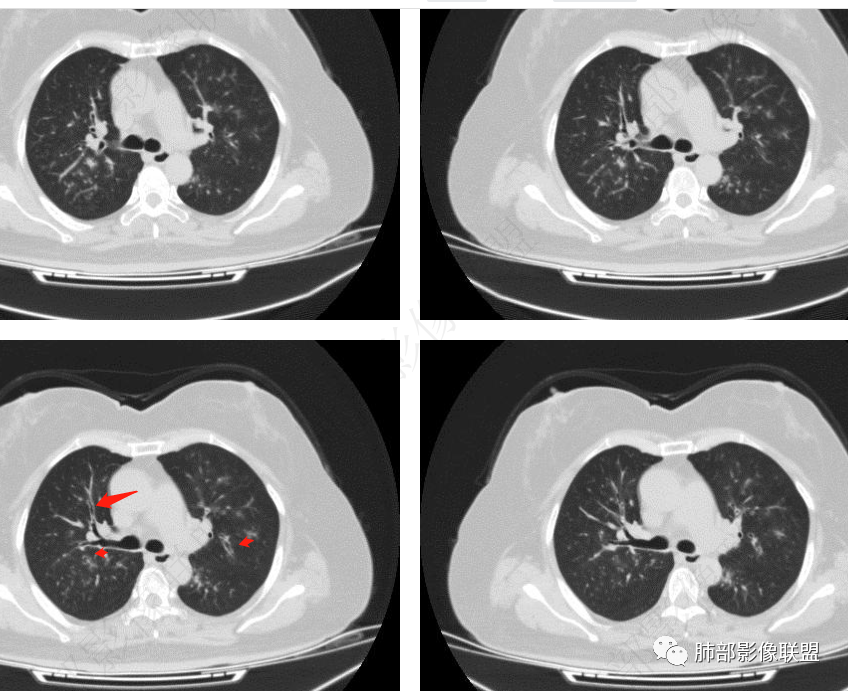

老年女性,发现白细胞升高两年,此次入院多次查外周血白细胞>30*10^9/L,淋巴降低,CRP显著升高,但病程中无发热,以细菌性炎不好解释;CT提示有脾大,结合外周血象,首先考虑存在血液系统疾病(白血病)基础,且未系统诊治;肺部CT提示双肺中轴间质增粗,伴随支气管管壁增厚?多发树丫及腺泡结节,部分呈点晕征,可见肺动脉分枝增粗,一元论考虑白血病肺部浸润;二院论考虑白血病并发气道侵袭曲霉。以患者病程进展看,更倾向于白血病肺部浸润。

肺动脉增粗,支气管有改变

左侧腔内有粘液栓,右侧支气管局部有扩张

支持气道病变,弥漫,支气管壁增厚,糖尿病,支持霉菌

肺动脉高压:性质待查,血象哪位老师解释一下,看右上支气管,怀疑以前都有过

1.病灶沿支气管分布的特点相当明显,相应支气管壁广泛增厚。这种与支气管关系极为密切的片影和/或结节影,常高度提示气道相关感染,如支气管肺炎。

2.患者两肺多发病变,具有广泛性。如此广泛分布更多见于免疫低下的机会性感染。

3.支气管壁广泛增厚对气道侵袭性曲霉病具有一定的提示意义。注意患者没有支气管扩张,临床也未提供IGE等实验室资料。

1.器官支气管管套样壁增厚和/或支气管扩张,注意壁增厚较均匀,和/或伴有播散性小片影及结节影,注意这些小片影或结节影边界有时较普通炎性病灶清楚。

2.可以阻塞支气管造成肺不张而酷似中央型肺癌。偶而可呈大范围毛玻璃样影。

3.易形成空洞,常无液平面。注意哪些一两周内出现的多发空洞病灶,形成空洞也往往靠边。